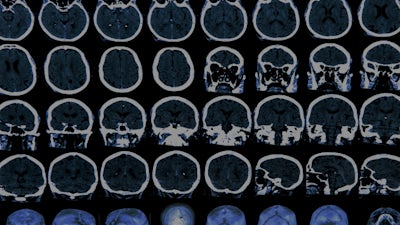

Mercury & Alzheimer's

Biochemist Boyd Haley, Ph.D., discusses his peer-reviewed scientific study which found that mercury could recreate all the same biochemical hallmarks as Alzheimer's disease.